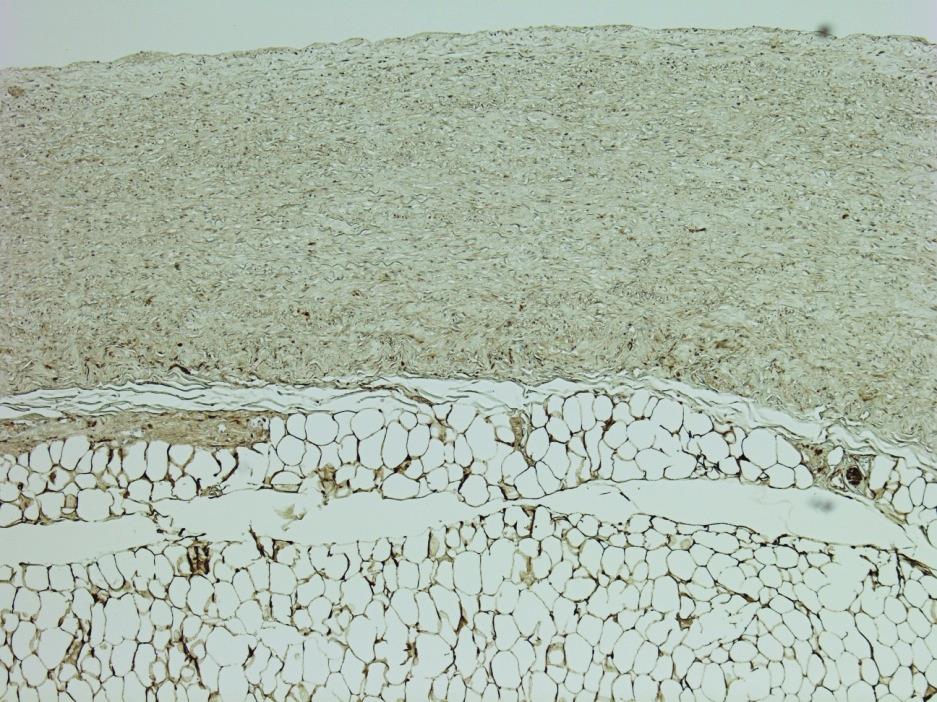

Радиочастотная денервация лёгочной артерии все чаще применяется кардиохирургами во всем мире при одновременной хирургической коррекции пороков сердца и аритмии у пациентов с высокой лёгочной гипертензией. Целью исследования является морфологическая оценка эффективности радиочастотной денервации легочной артерии с помощью иммуногистохимического окрашивания ганглионарных нервных сплетений и вегетативных нервных волокон антителами к белку S-100. Материалом исследования послужили 30 лёгочных стволов людей, умерших от внесердечной патологии, в возрасте от 31 до 65 лет (секционный материал, полученный при плановых аутопсиях. После чего проводили иммуногистохимическое окрашивание на Иммуностейнере Leica Bond MAX с поликлональным антителом к белку S-100. Легочные нервные волокна после окрашивания на белок S-100 в основном обнаруживались по левому латеральному краю лёгочного ствола, медианные значения Sотн. = 5,72% (95% ДИ 4,27–8,95). В передней и задней стенках лёгочного ствола встречается незначительное количество тонких нервных волокон, Sотн. = 0,99% (95% ДИ 0,48–0,93), p < 0,0000. В срезах лёгочных стволов в участках, подвергнутых радиочастотной денервации, нервные волокна на белок S-100 не окрашиваются. Это связано с тем, что термическая коагуляция белков привела к потере специфической трехмерной структуры и антигенных свойств, что является доказательством разрушения вегетативных нервных волокон лёгочного ствола. Количественная иммуногистохимическая оценка повреждения нервных волокон с использованием антител к белку S-100 позволяет оценить эффективность радиочастотной денервации лёгочной артерии.